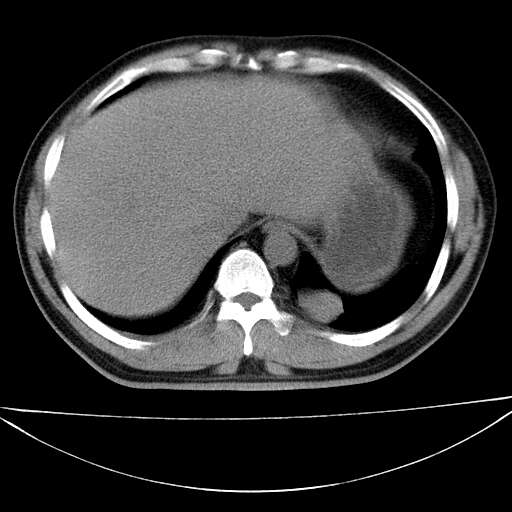

标题: CT21921:腹膜后腔肿物。患者男39Y。体检。增强扫描时间欠准

左侧膈肌脚外缘见一结节样软组织影,密度较均匀,与胸膜关系稍密切,增强轻度强化;考虑来自胸膜良性病变(胸膜纤维瘤可能)。建议加扫胸部ct检查。

2、左下膈肌脚外缘结节状病变,与胸膜交界面呈锐角,胸膜下脂肪线可见,定位于肺内,考虑支气管囊肿或肺隔离征可能性大。

膈疝

左肋隔角占位,考虑胸膜间皮瘤

1)考虑左肺下叶后基底段(或左下胸后壁胸膜)软组织团块,性质待定;建议行进一步检查。2)左肾结石。

左膈肌连续性中断,左侧膈疝可能性大.

左膈肌角后腹膜腔见肿物影,其内见脂肪密度灶及软组织密度灶,强化不明显。病灶大部在后腹膜内。考虑异位嗜铬细胞瘤或脂肪肉瘤、畸胎瘤

考虑左肺下叶后基底段肺隔离症?胸膜间皮瘤?